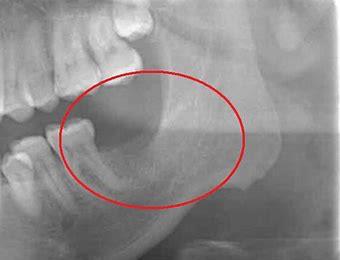

Diagnosis of cavitation

The best technology we have today to diagnose cavitations is a 3D cone beam CT scan. I recommend that anyone who had wisdom teeth removed, trauma to the jaw, and/or root canals, should have a dental cone beam CT scan to properly evaluate the health of the mouth and jaw. A standard x-ray image only provides very limited information. It is a onedimensional view of the bone, with little detail. Research shows that regular dental 2-dimensional x-rays are not likely to show a problem unless at least 40 to 50 percent of the bone tissue in an area is altered. On an average, dental 2D X-rays only show approximately 50% of the problems. Furthermore, because the effects of toxins tend to be systemic, and pain may be felt in another area, and there is nothing to draw a dentist’s attention to the site of the cavitation. Due to the insidious symptoms and the fact that most dentists don’t have a CT scan machine and are not trained to read CT scans, cavitations are largely overlooked. They are not included in a standard dental screening. Therefore, in order to achieve optimum health, a cone-beam CT scan is a must to rule out silent chronic inflammatory problems.